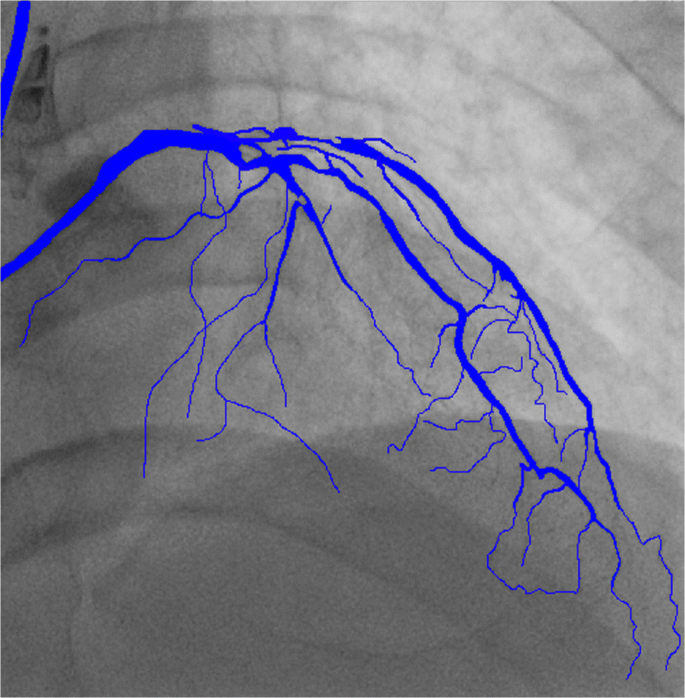

Figure 6 shows the segmentation result of one image. Figure 7 shows the results of a video sequence. From the results we can see the detail of the coronary arteries. To evaluate the performance of the vessel segmentation, we compute the sensitivity and the accuracy, which are also calculated in[31].

where TP is the number of true positives, TN is the number of true negatives, FP and FN represent the number of false positives and false negatives. In addition, we also compute the IoU overlap to measure segmentation performance as shown in Fig. 5. Table 1 shows the performance comparison with other method. What needs to be explained here is that we use not only the public data set DRIVE [28] but also our own data set. Our work achieves 0.8739 in Sen, 0.9895 in Acc, the average values of TP, TN, FP, and FN are 3929912.0, 115029685.0, 747732.0, and 860167 for all the test frames. From the performance of the results, the accuracy of our method is significantly improved. The performance benefit from the algorithom architecture in [23] and the enlarged dataset.